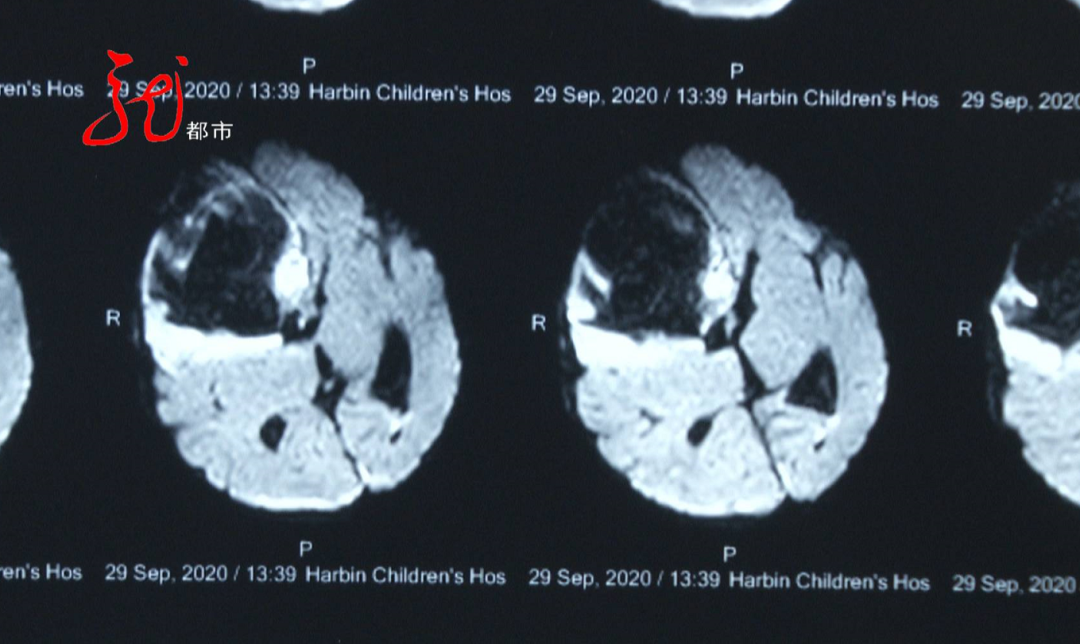

就考虑维生素K缺乏导致的脑出血,然后做了一个核磁,核磁我们会看到这些片子,这孩子已经出血很大量了,那就说明这孩子是隐匿出血、缓慢出血,总的出血量实际上占脑容量的,已经达到1/5了。

确诊当天,桃桃就接受了手术治疗,将脑内的血肿引了出来。

但是她这块我们应该看到还有一个整个破坏的灶,现在孩子挺好,我们现在就是说,孩子来的时候是抽搐的,住院一直到现在已经10多天了,到今天为止没有抽搐过一次,我们现在预防她今后一个癫痫的发生。

目前,桃桃的肢体活动、意识状态、疼痛刺激反应良好,身体还在进一步的恢复当中。医生介绍,桃桃得的是“晚发性维生素K缺乏性出血症”。